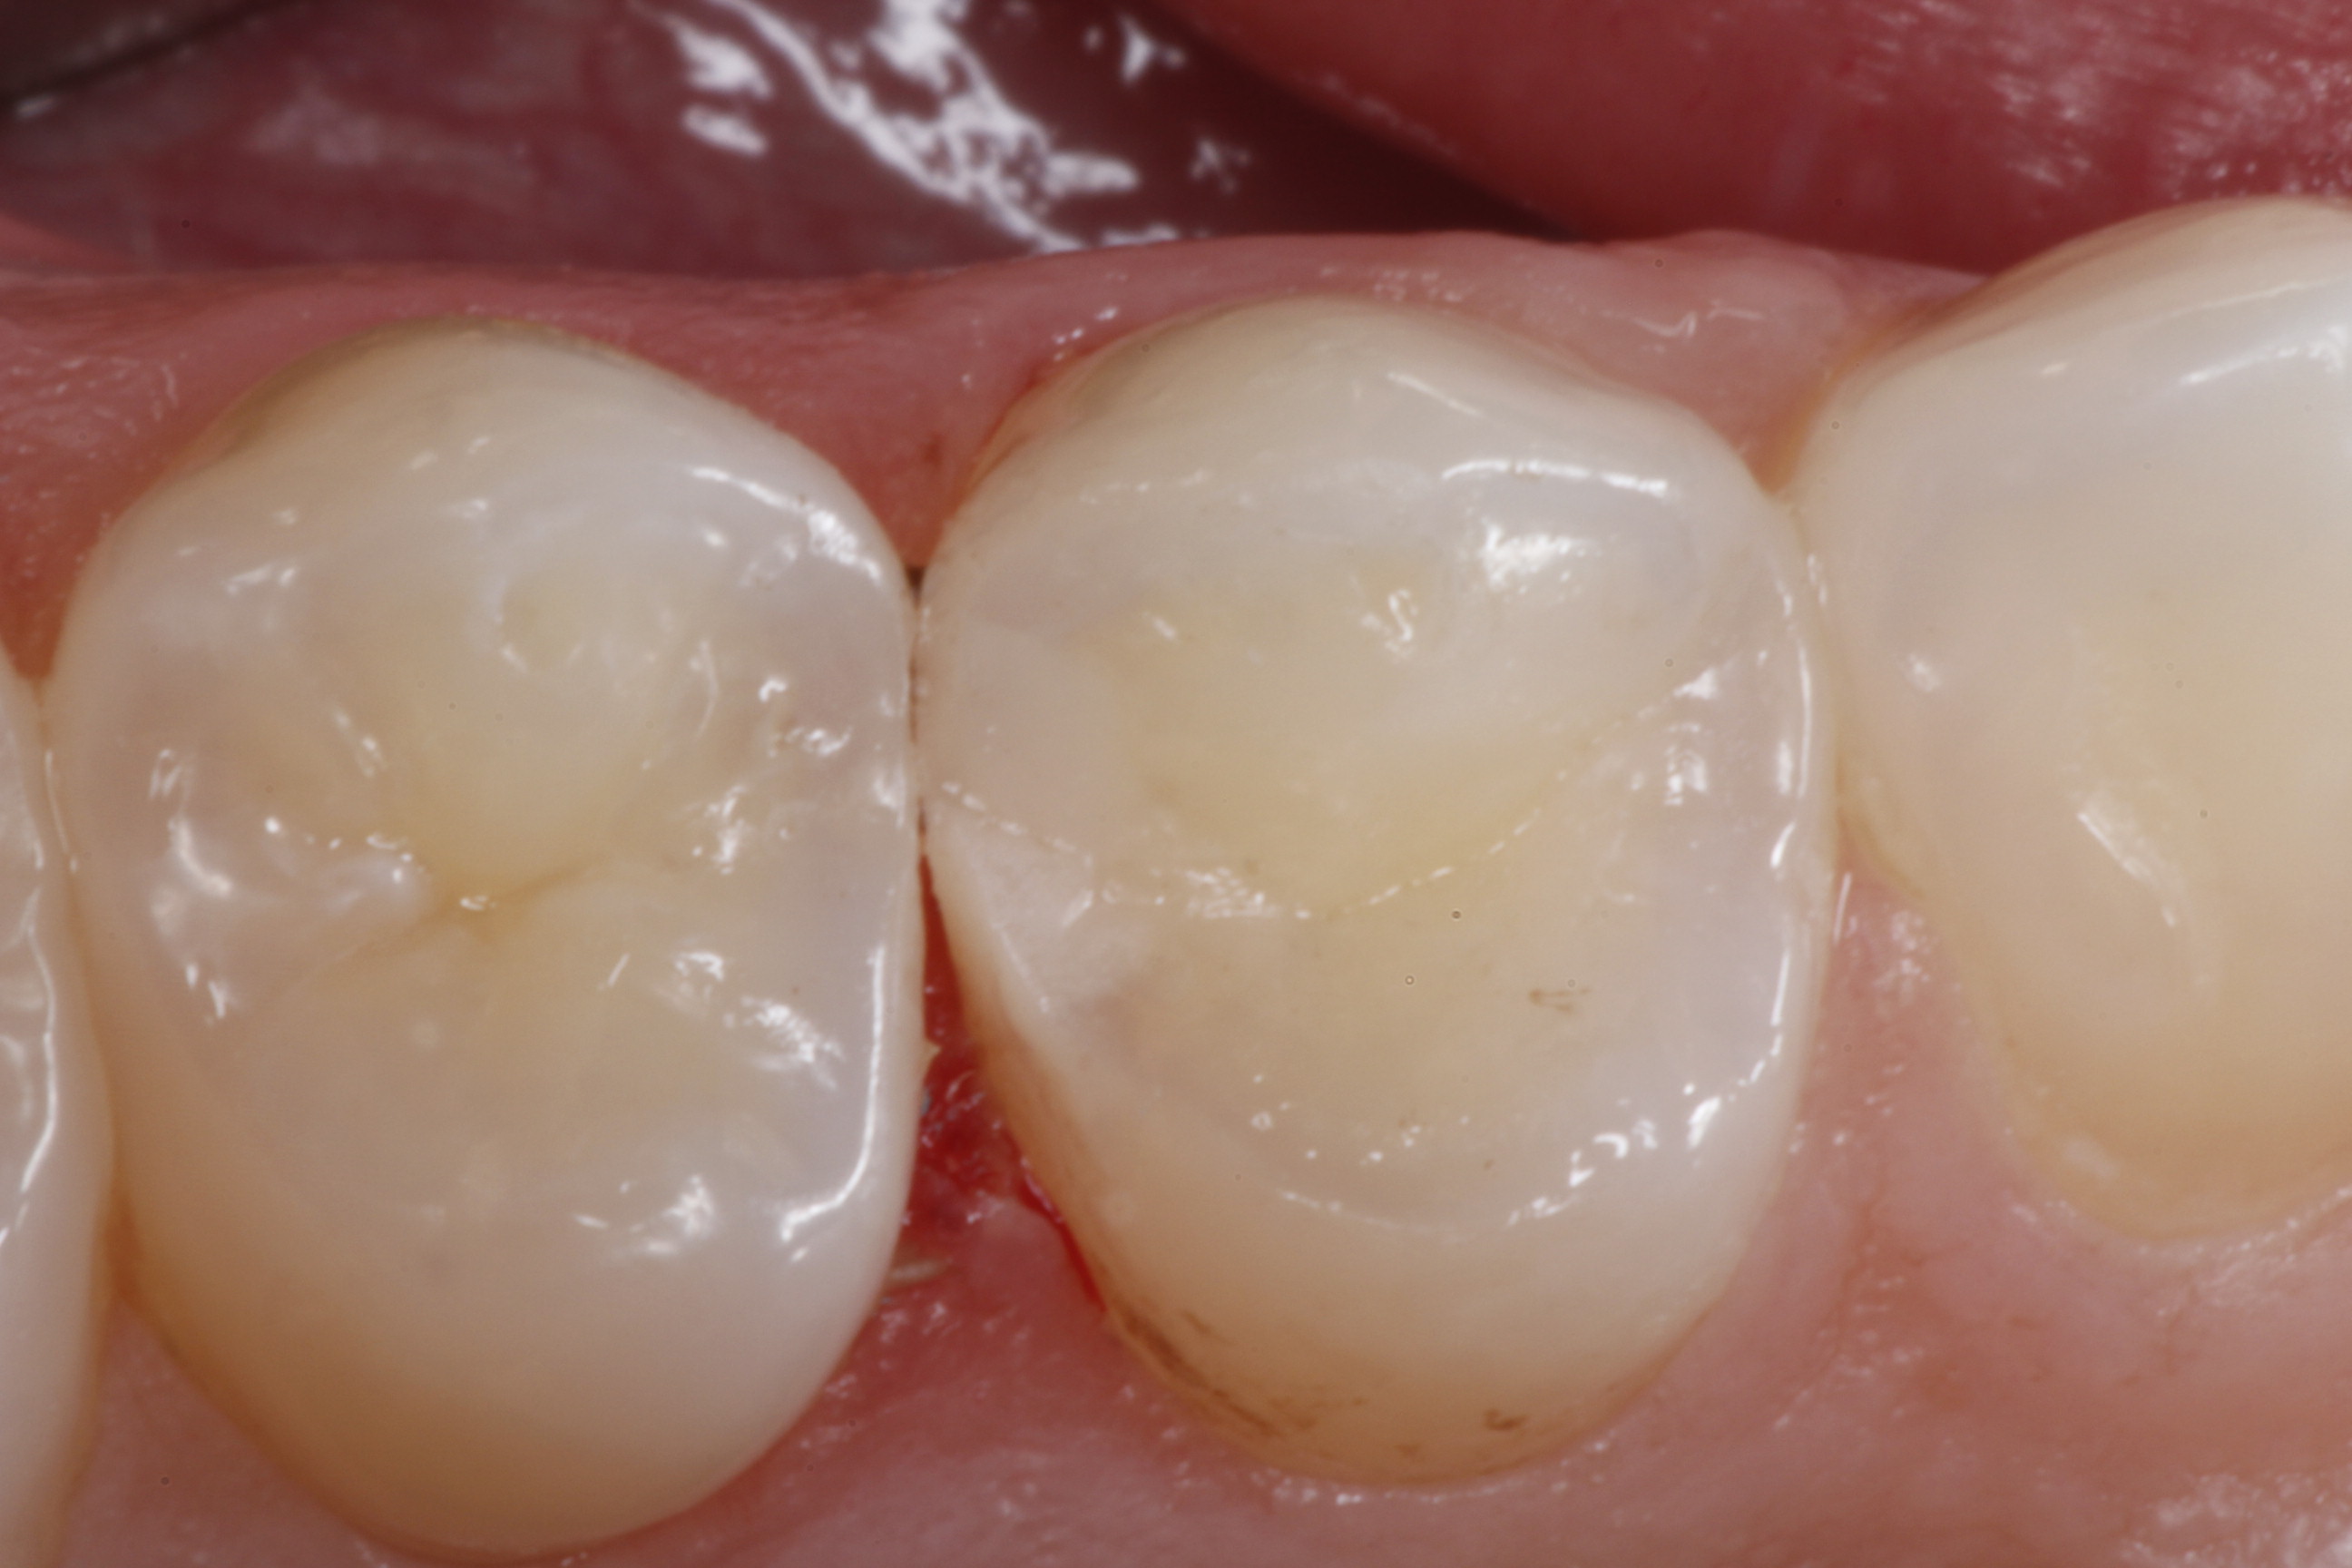

Fig 20. A distal-occlusal cavity preparation in tooth No. 29 and a mesial-occlusal-distal cavity preparation in tooth No. 30 are both shown from the occlusal aspect. A diode laser has been used interproximally to create supragingival margins to aid in precise gingival placement of the restorative material.

Figure 20

Fig 21. A Giomer bulk-fill paste-type composite is shown being placed with a composite placement instrument in the distal-occlusal cavity preparation on tooth No. 29.

Figure 21